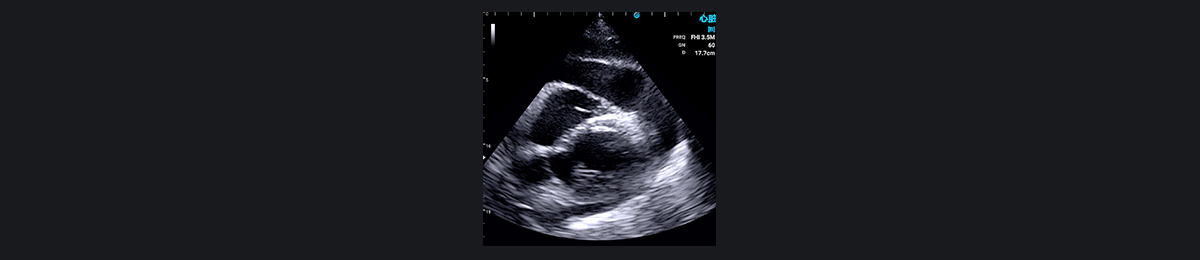

二叶式主动脉瓣